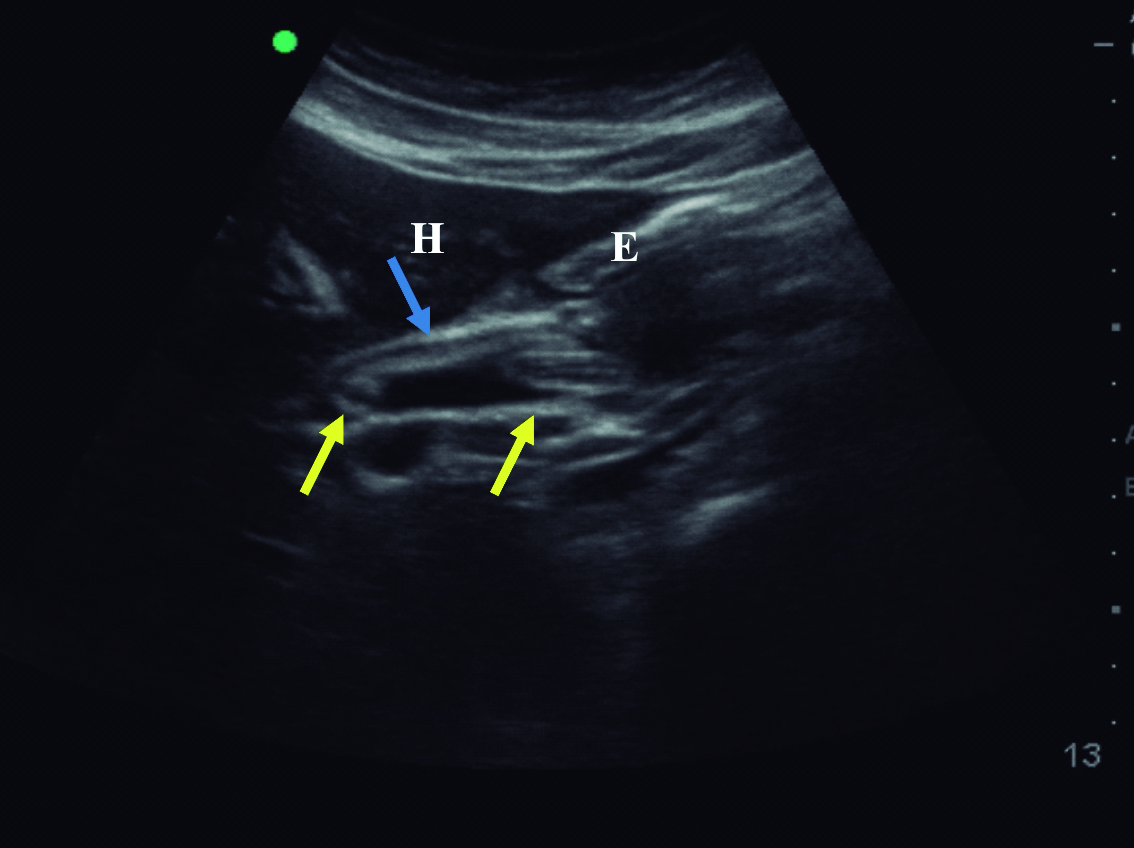

Con estos hallazgos, el equipo tratante solicita tomografía computarizada para completar valoración. La misma se realizó sin medio de contraste, dado dificultades en la punción de la paciente. Se observa imagen lineal hiperdensa dentro de la luz del colédoco, el cual se encuentra dilatado con un diámetro máximo 12mm (Fig. 2)

Figura 2. Tomografía computarizada plano axial sin medio de contraste

a y b) Se observa imagen lineal hiperdensa que corresponde

al Ascaris dentro de la luz de la rama izquierda del conducto

hepático y dentro del conducto hepático común (*).

La tomografía computarizada no es el método de elección para el diagnóstico de la ascaridiasis en la vía biliar y si la ecografía demuestra la imagen típica debería evitarse su uso o indicarse una resonancia magnética si hay dudas de los hallazgos. (13) De todas formas, la tomografía permite en algunos casos identificar los parásitos dentro de la vía biliar y valorar posibles complicaciones. La identificación de los parásitos es más sencilla en la tomografía sin contraste, en la que aparecen como estructuras tubulares hiperdensas rodeadas de bilis hipodensa. En los cortes axiales, al igual que en la ecografía, se visualiza la típica imagen en diana dada por el parásito dentro de la vía biliar dilatada. (14)